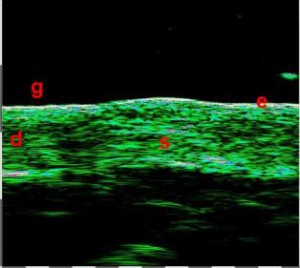

-Υπέρηχος Υψηλής Συχνότητας (HFUS) και Ιστολογία